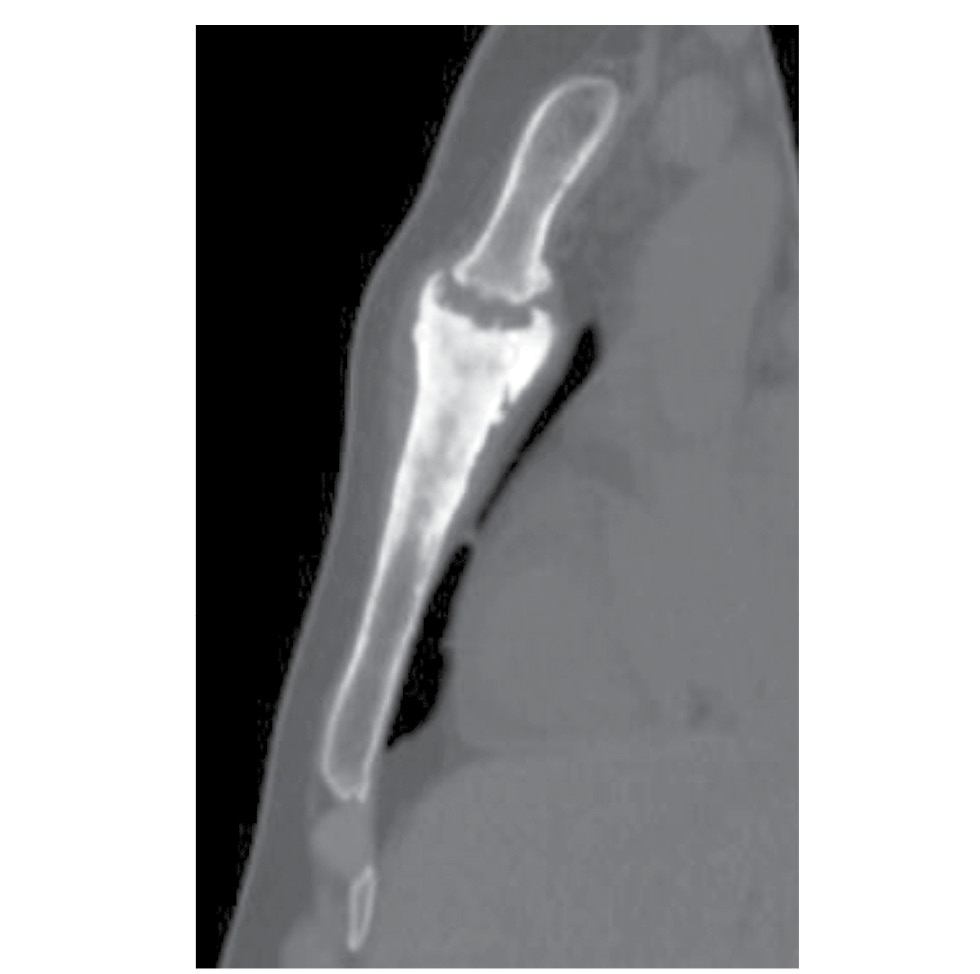

При осмотре: в области верхней трети грудины определялись отёчность и зона гиперемии размером 7×4 см. При пальпации боли усиливались. По результатам компьютерной томограммы от 07.04.2020 (рис. 1) выявлены структурные изменения костей, формирующих сочленение рукоятки и тела грудины.

Рис. 1. Мультиспиральная компьютерная томограмма грудины от 07.04.2020. Сагиттальный срез, 0,625 мм, мультипланарная реконструкция.

Fig. 1. Multi-spectral computed tomography picture of the sternum from 07.04.2020. Sagittal partition, 0.625 mm, multiplanar reconstruction.